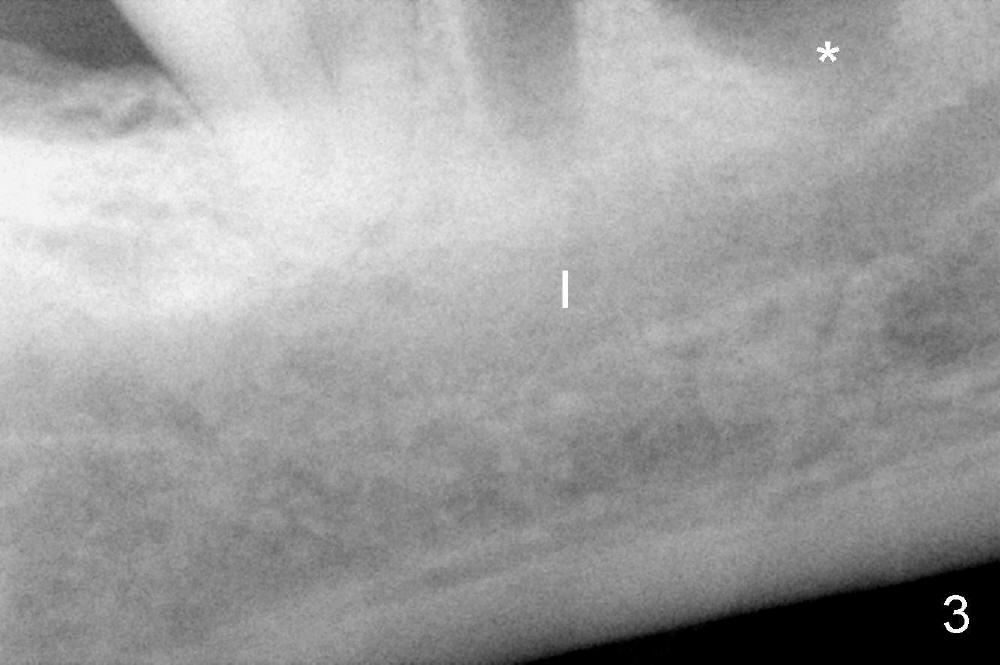

There are three potential spaces for the immediate implant: the mesial and distal sockets and the septum. First at all, the tooth should be extracted with curettage of granulation tissue from the mesial apical lesion. The latter turns out to be difficult, since the bottom of the mesial socket has abrupt transition into a narrow neck, which look and feels like the IAN. To determine the depth of the lesion relative to the IAN, PA is taken (Fig.3) without too much information. When a radiopaque material in placed in the mesial socket (Fig.4 M), the lesion has apparently not extended to the IAN. Curettage of the remaining granulation tissue is now an easy task. Finally bleeding comes from a small hole, as indicated by arrowhead. Therefore the special structure is a branch of the inferior alveolar vessels.